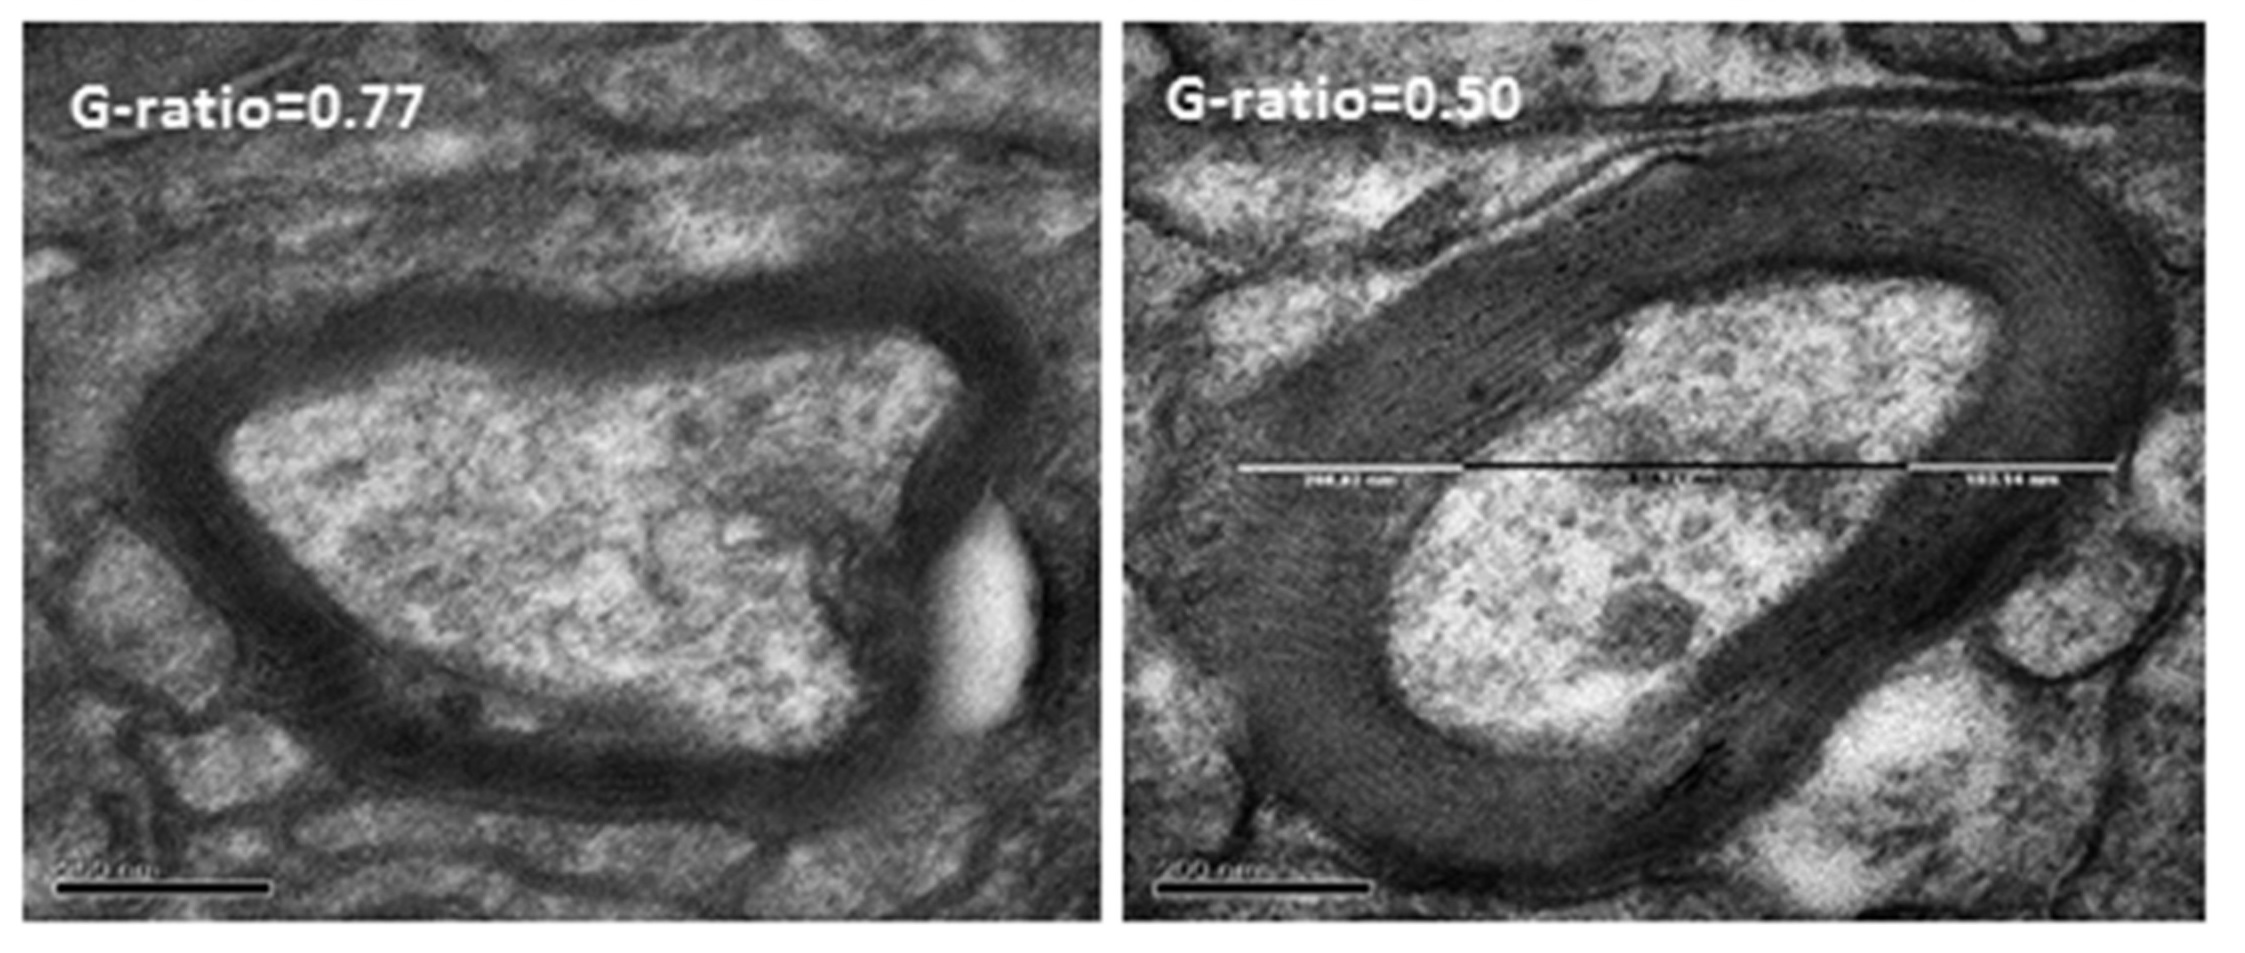

研究人员发现大鼠形成模式记忆后,牠们再学习两组新的食物和特定收藏地点配对的速度会快很多,训练一节就能掌握。研究人员使用免疫组化(immunohistochemistry)和透射电镜等技术解析大鼠大脑变化,发现大鼠在学习和记忆模式的建立过程中,由于大脑皮层区域的神经活动增强,可以促进少突细胞增生和细胞分化(differentiation),从而促进髓鞘形成,令髓鞘显著增厚。